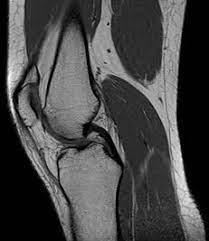

In cazul afectiunilor musculare si osteoarticulare ultrasonografia si rezonanta magnetica nucleara sunt cele mai des utilizate. Odata cu realizarea acestor examinari, de cele mai multe ori sunt decelate si cauzele aparitiei durerii articulare sau musculare.

Fig 3. Sectiune RMN - genunchi

De aceea, cel mai important obiectiv ar trebui sa fie cel de diagnosticare corecta si initiere a tratamentului de catre medicul specialist, la care se adauga o buna comunicare intre pacient si medic, ce au ca scop rezolvarea episodului dureros si scaderea tendintei de automedicatie pentru acea simptomatologie dureroasa considerata de pacient ca una usor de abordat si de rezolvat.

Durerea in afectiunile osteoarticulare este, doar un simptom ’’ care alerteaza pacientul si il fac sa se prezinte la medic. Este total gresit sa se trateze doar simptomatologia dureroasa prin automedicatie, fara a se efectua investigatiile medicale necesare pentru stabilirea cauzei care a provocat acest simptom